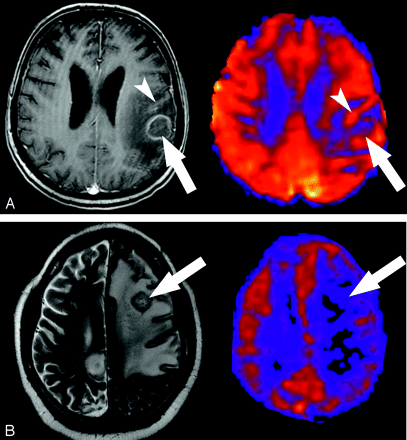

低级别胶质瘤级别(二级和三级)是决定其预后的重要因素,也影响患者的个体化治疗。过去常规MRI特征用于区分低级别胶质瘤级别,主要根据肿瘤部位、侵...